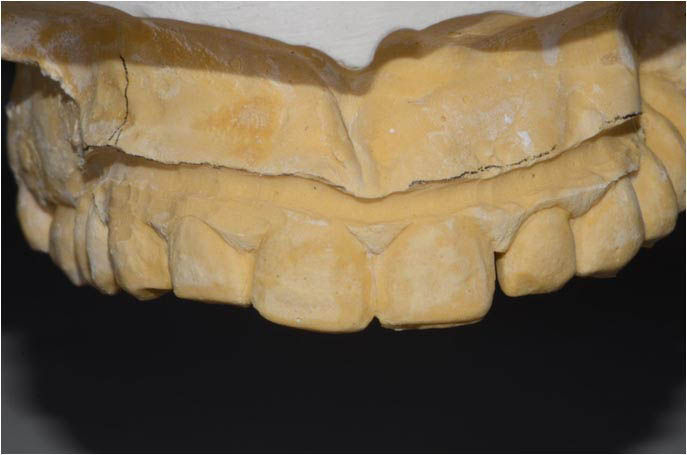

Model obtained from initial impressions, mounted in the articulator.